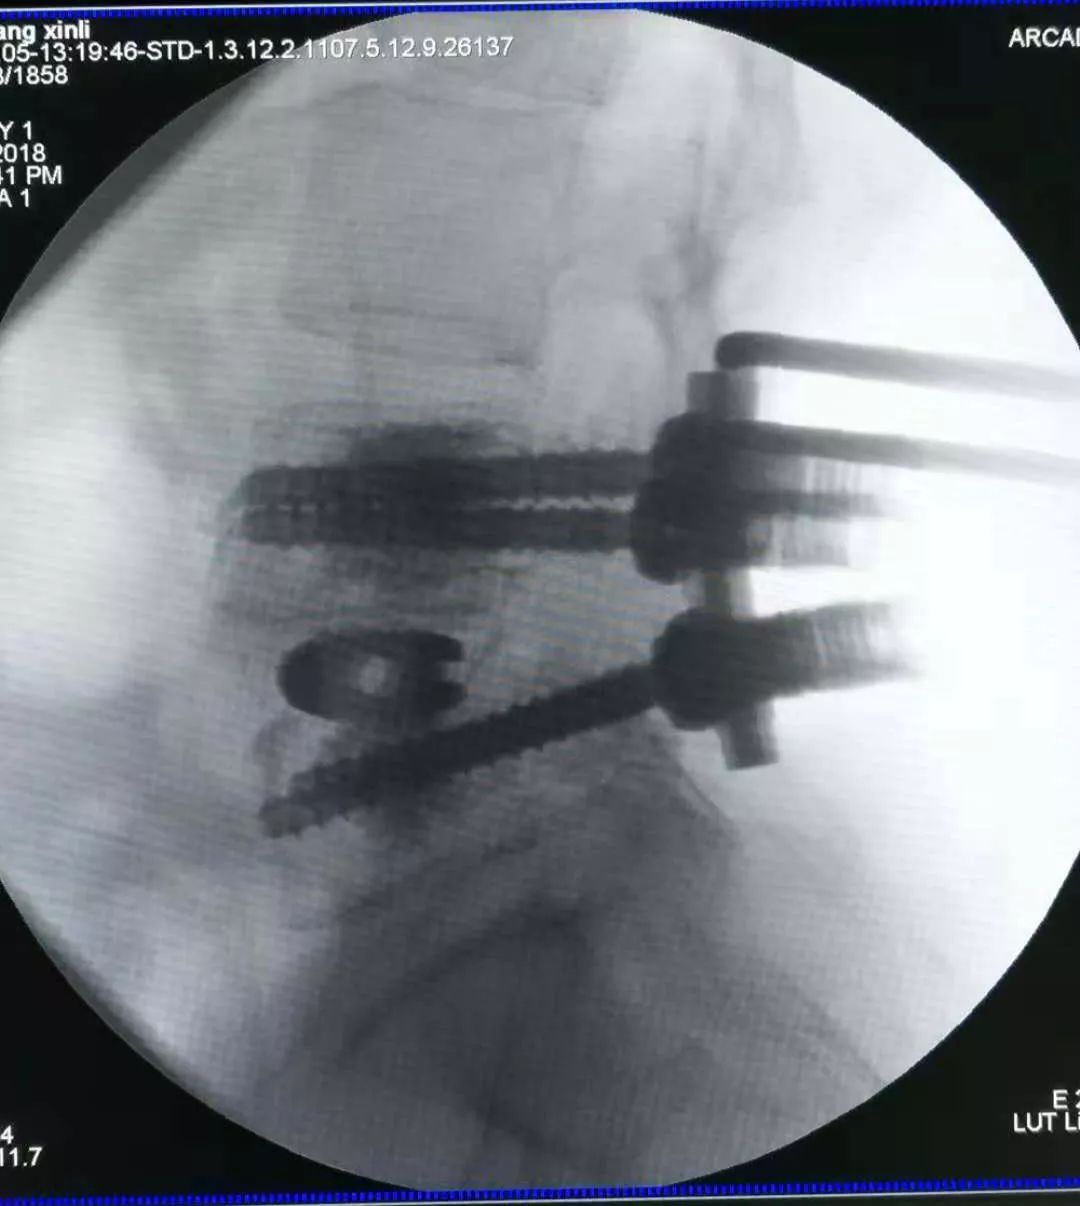

术中情况

术后CT示腰4-5椎间融合器固定在位,腰4/5椎体内骨水泥填充于螺钉周围,螺钉固定妥。

本病例中,患者腰4椎体II度滑脱,伴腰4-5椎间盘突出,相应水平椎管狭窄,手术指征明确。患者合并重度骨质疏松,故手术中使用骨水泥钉固定的同时在螺钉周围注射骨水泥增强螺钉把持力。

患者术后复查CT示骨水泥钉固定在位,腰4椎体复位良好,椎管减压充分!患者诉腰部及下肢疼痛明显减轻,四肢活动,肌力肌张力同术前!